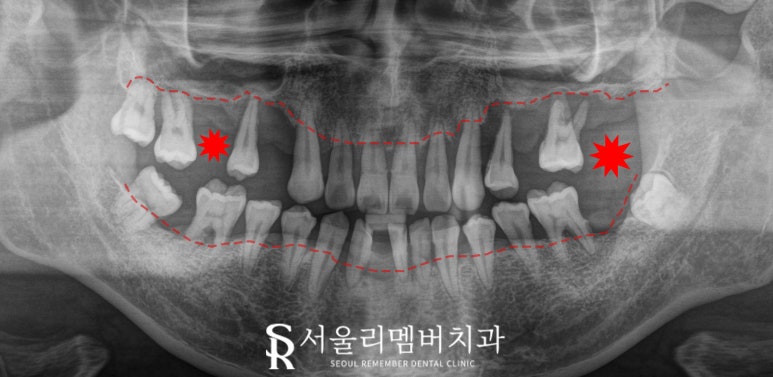

파노라마에서 보이는 것처럼

꽤 오랜 기간 구강관리를 하지 못해

다수의 치아를 상실하고,

남아있는 이들조차

대부분 심하게 흔들리고 있습니다.

특히 치주 질환(잇몸병)이 매우 심각해

치근 끝까지 잇몸뼈가 흡수된 부위가 여러 곳 있었고,

상악(위턱)에는 건강하게

저작 기능을 수행할 이가

하나도 없어 보입니다.